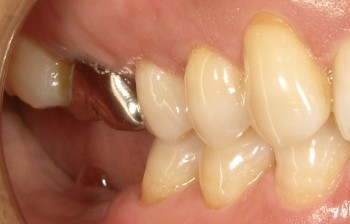

インプラントの術前・術後 Kさん